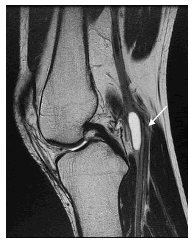

Con estos hallazgos, se planteó como primera posibilidad una enfermedad quística de la adventicia de la arteria poplítea, con estenosis crítica secundaria. Posteriormente, una resonancia magnética (RM) de rodilla demostró alteraciones similares (figura 2). En la angiografía por RM de la región poplítea se observó, además, la zona de compresión y ausencia de flujo segmentario en la arteria poplítea (figura 3).

Los quistes pueden ser vistos en la pared de la arteria poplítea, pero también en sus ramas, como las arterias geniculadas 8. Los quistes se observan hiperintensos en imágenes ponderadas en T2 (T2WI), mientras que, en imágenes ponderadas en T1 (T1WI), presentan intensidad de señal variable según las diferencias en su contenido mucoide 8,10. En los quistes de mayor tamaño se pueden observar tabiques en su interior 8. En secuencias contrastadas con gadolinio, no presentan realce o solo captación en anillo 10.